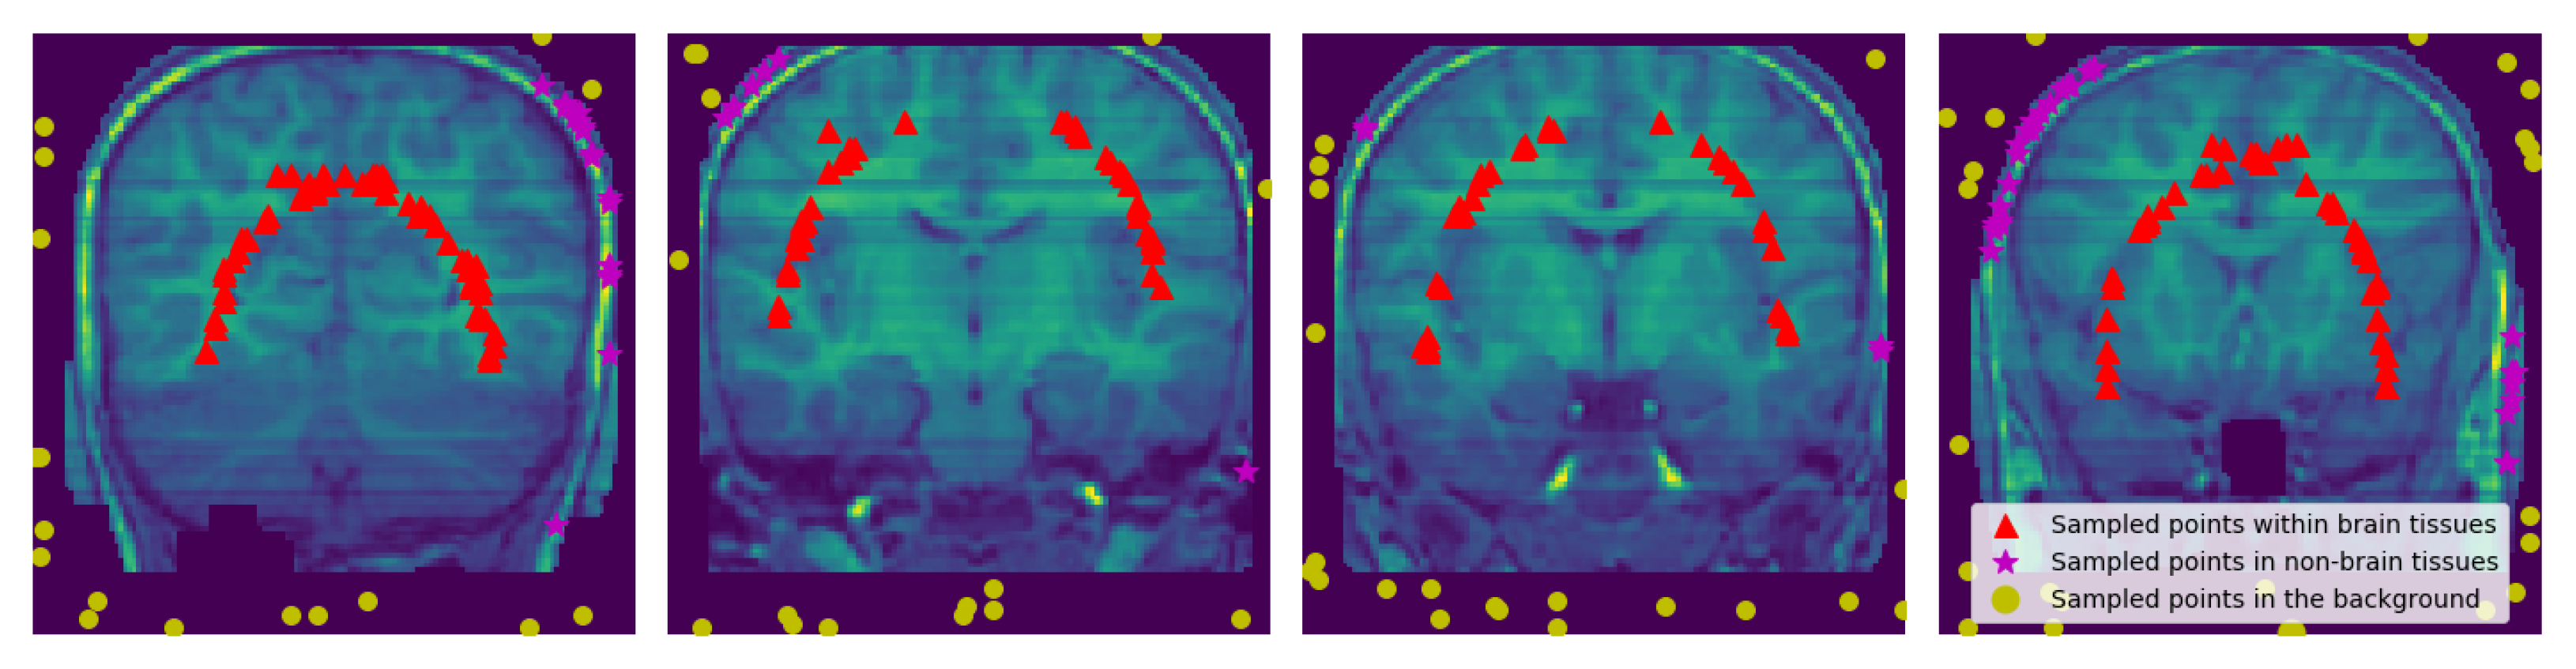

To obtain points in the non-brain tissues we use all the discrete 3D edge-like points distributed at the surface of the head and pull them inside towards the non-brain tissue by . The pulled points are rechecked if there is any point with the intensity value of zero it is removed. See Figure 4 and Figure 5.

Figure 5.

Sampled Points: 2D visualization of the representative coronal section from MRI image of a single subject (IBSR data) showing the sampled points within the brain region, within non-brain tissues, and in the background. and values were set to 15 and 3, respectively. Notice the removed part of the skull and the brain from some slices.

Figure 9 and Figure 10 show experimental result of one subject from IBSR and OASIS, respectively. The challenging part is to sample within the non-brain tissues because some parts of the brain and non-brain tissues have been removed (see row one in Figure 9). Some points sampled from the non-brain tissues are likely to be taken from the brain when is applied. For Figure 9 and Figure 10, and .